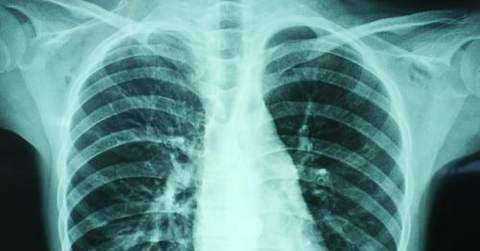

viêm phổi thường đề cập đến viêm phổi do nhiễm trùng các vi sinh vật khác nhau. Các vi sinh vật gây viêm phổi không chỉ bao gồm vi khuẩn mà còn cả virus. Những vi sinh vật này có thể tồn tại trong môi trường xung quanh chúng ta, và cũng có thể bị xâm chiếm trong cơ thể chúng ta, chẳng hạn như miệng, khoang mũi, v.v … Khi sức đề kháng của cơ thể giảm, chẳng hạn như làm việc quá sức hoặc lạnh, rất dễ bị viêm phổi.

Đặc biệt, các nhóm đặc biệt có sức đề kháng yếu, như trẻ em, người già hoặc bệnh nhân mắc các bệnh tiềm ẩn như bệnh tiểu đường và khối u ác tính. Bởi vì những người cần dùng glucocorticoids và thuốc ức chế miễn dịch trong một thời gian dài trong các bệnh khác dễ bị viêm phổi, đặc biệt là viêm phổi do virus và nấm.